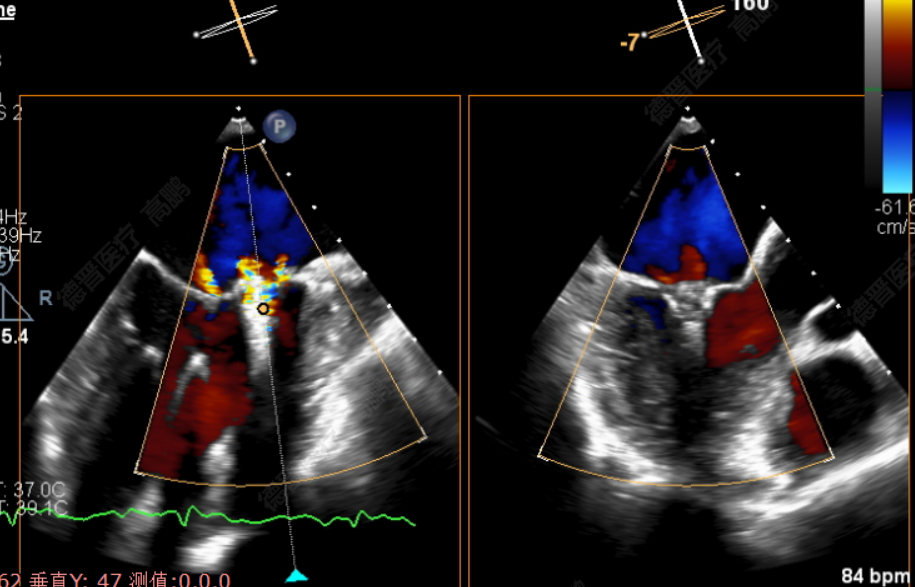

患者为75岁老年男性。反复气促、胸闷2年余,加重1月就诊福建省立医院。经胸心脏彩超提示:二尖瓣后叶重度脱垂伴返流4+、后叶腱索断裂;经食道超声心动图提示:二尖瓣后叶P2区重度脱垂伴返流4+。既往有高血压病、冠心病病史。

患者为72岁老年男性,反复胸闷、气促1年,加重1周就诊福建省立医院。心脏彩超提示:二尖瓣前叶脱垂伴返流4+;食道超声心动图提示:为二尖瓣后叶A1区偏前联合交界处重度脱垂伴返流4+。既往有COPD(肺功能提示重度阻塞性通气功能障碍)、高血压病病史。